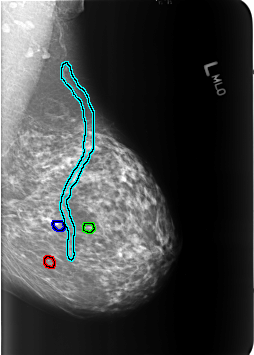

B_3239_1.LEFT_MLO

FILE: B_3239_1.LEFT_MLO.OVERLAY

TOTAL_ABNORMALITIES 4

ABNORMALITY 1

LESION_TYPE CALCIFICATION TYPE PUNCTATE DISTRIBUTION N/A

ASSESSMENT 2

SUBTLETY 4

PATHOLOGY BENIGN_WITHOUT_CALLBACK

TOTAL_OUTLINES 1

BOUNDARY

ABNORMALITY 2

ABNORMALITY 3

ABNORMALITY 4

LESION_TYPE CALCIFICATION TYPE VASCULAR DISTRIBUTION N/A